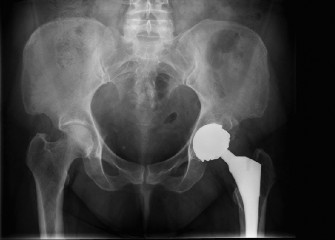

A 50-year-old female underwent metal-on-metal (MoM) total hip arthroplasty 1 year ago for osteoarthritis. Her…